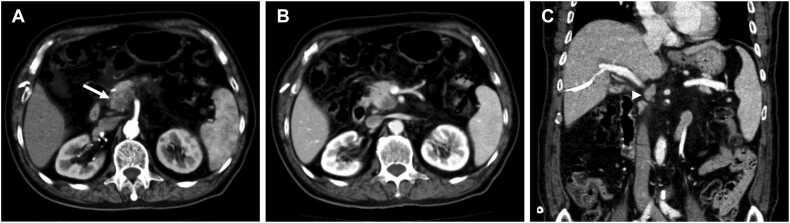

A total of 149 patients were evaluated (median age: 67 years; interquartile range: 41-89 years; 82 men), among whom 70 (47.0 %) experienced early recurrence. Rim enhancement, tumor necrosis, peripancreatic tumor infiltration, and suspicious metastatic lymph nodes, were independently associated with early recurrence. When any two or more of these four significant imaging features were combined, the specificity was 86.1 % (68/79) and the sensitivity was 88.6 % (60/70). DFS and OS were significantly worse in PDAC patients with two or more of these features compared to those with none or only one (all log-rank  < 0.001).

A combination of two or more imaging features such as rim enhancement, tumor necrosis, peripancreatic tumor infiltration, and suspicious metastatic lymph nodes, could be used as a prognostic imaging marker for early recurrence, demonstrating effective diagnostic performance and an association with DFS and OS after pancreatoduodenectomy of PDAC.